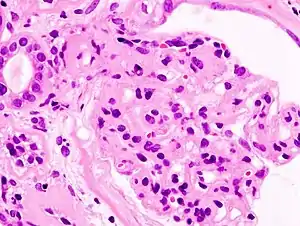

![]() Гістопатологічне зображення нирок при діабетичному гломерулосклерозі з нефротичним синдромом. Забарвлення гематоксилін-еозином Гістопатологічне зображення нирок при діабетичному гломерулосклерозі з нефротичним синдромом. Забарвлення гематоксилін-еозином | |